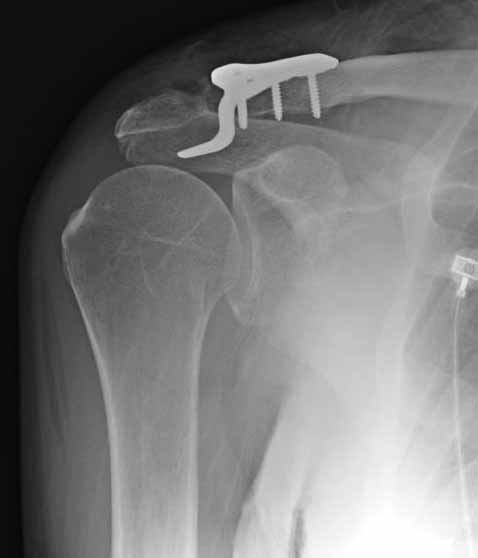

Из заданного вопроса в этом посте я понял, что разговор идет по поводу “методики применения ключичной пластины с крючком при акромиальных переломах”, т.е не ведется разговор “по поводу лечения косых переломов ключицы”.

Если так, тогда Юрий прав, методов лечения акромиона пластинами нельзя было найти. Обычно изобретали из реконструкционных пластин 2.7 или 2.4 мм толщиной. Такая фиксация адекватно удерживает перелом акромиона. Только недавно компания Acumed создала пластину для переломов акромиона, здесь линк: http://www.acumed.net/sites/default/files/literature/brochure-surgical-technique/CPS00-11-A.pdf.

По поводу пластины с крючком, Ваше заключение "не вижу препятствий для фиксации акромиального косого перелома ключицы для МОС использовать пластинку с крючком" вызывает сомнение.

Предназначенную для лечения повреждений связочного аппарата акромиально-ключичного сочленения пластину можно применить не при всех переломах акромиального конца ключицы. Потому что имплант рассчитан на интактную ключицу и не для переломов ключицы. Пластина короткая, не покрывает медиальный диафизарный фрагмент ключицы и за счет тракции стерноклеидомастоидеус такая фиксация прорвется через несколько дней.

Имя     : 3 Clavicle AC post op 2.jpg